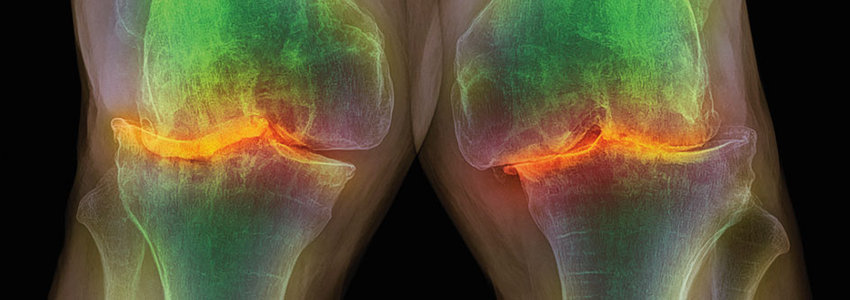

Knochendichte & Frakturrisiko im Fokus

Osteopenie betrifft Millionen, doch eine Behandlung ist nicht immer Pflicht. Entscheidend ist das individuelle Frakturrisiko – Tools wie der FRAX…